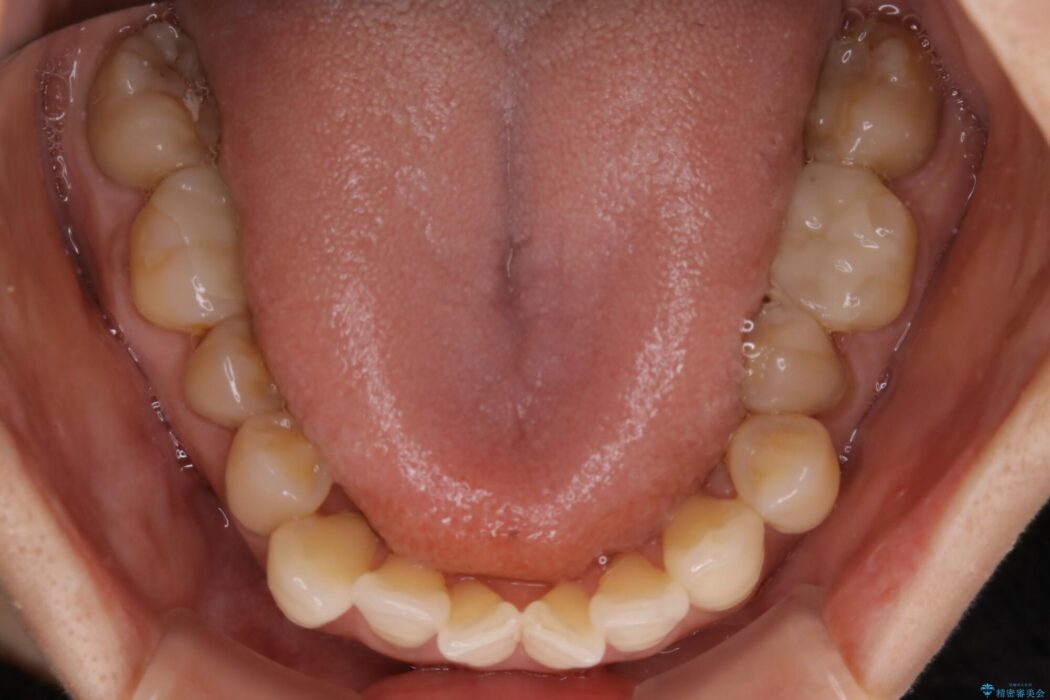

全体的に歯列が狭窄しており、本来外側に覆いかぶさっている上の前歯が内側に入り込んでいました。

歯列弓全体の形状を整えるとともに歯の大きさもコントロールすることで非抜歯にて矯正を行いました。

歯並びが悪くなる原因の一つに「歯列弓の狭窄」というものがあります。

奥歯や前歯が内側(舌側)に倒れ込んでしまったり、歯が生えてくる位置が内側になってしまうことにより歯並びのアーチが狭くなってしまうことを言います。

このような場合、歯並びのアーチを拡大してあげるだけでもガタつきを無くすためのスペースがかなり作れることがあります。